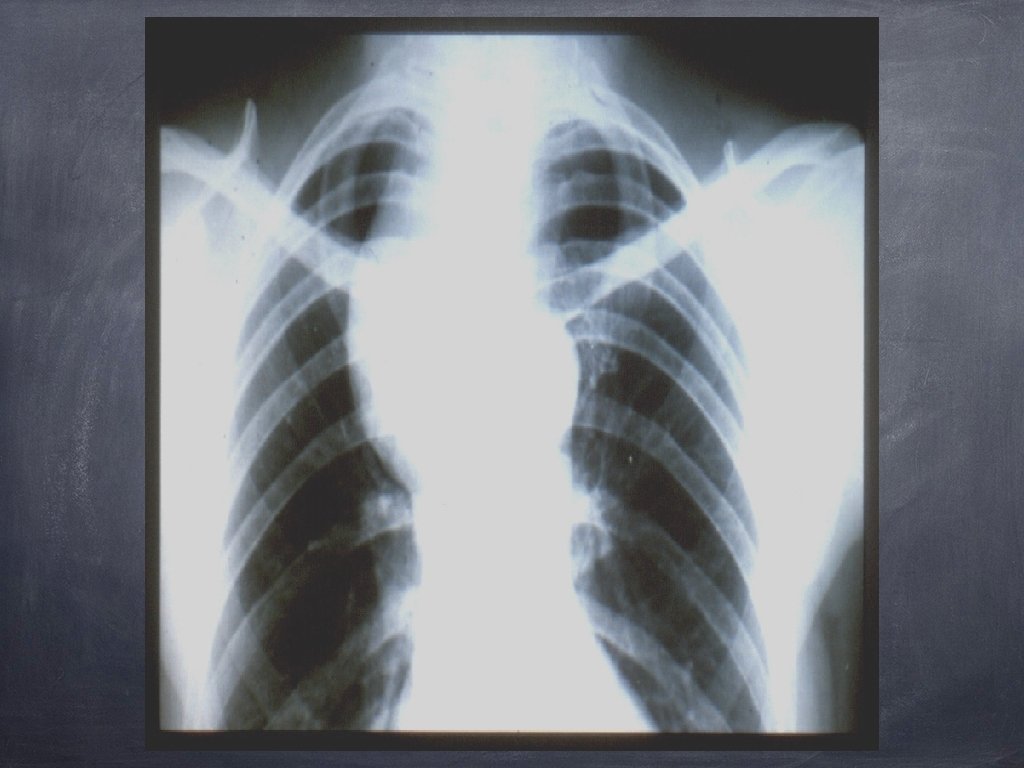

Semnul cervico-toracic